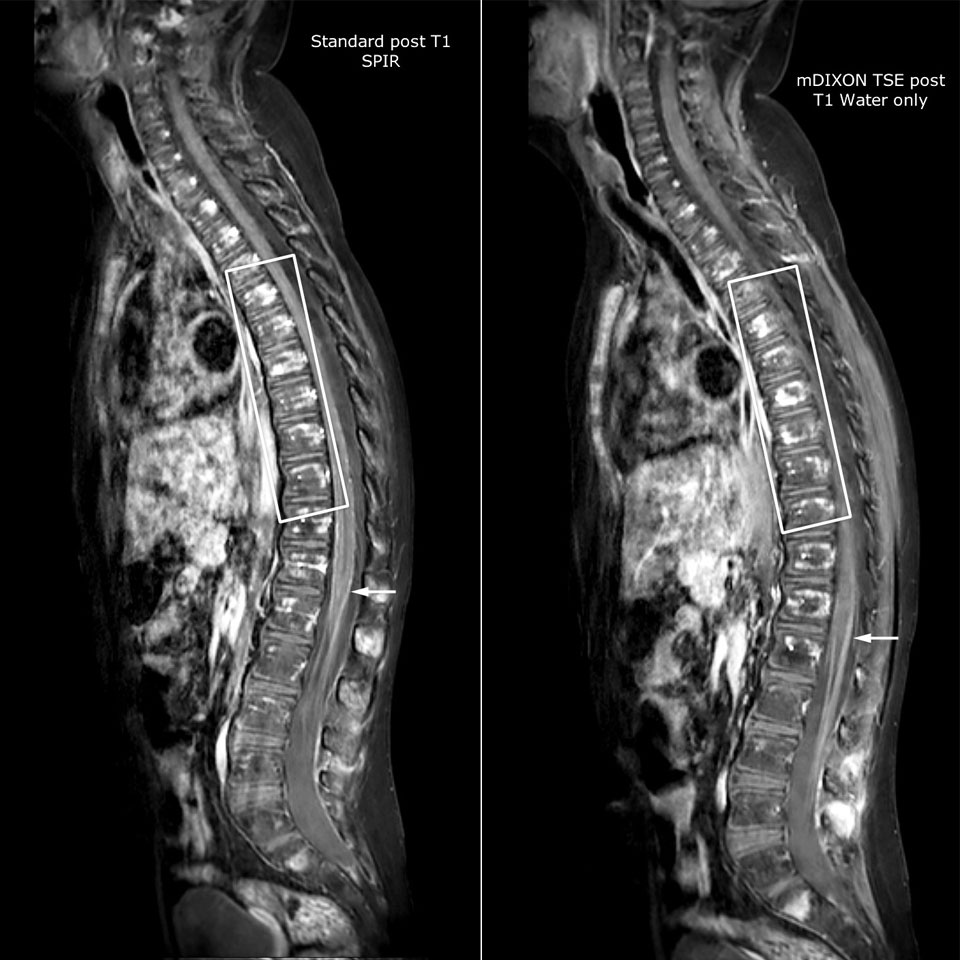

Philips mDIXON TSE is a two-point DIXON technique that separates water and fat signals, for time-efficient fat-free imaging, even in challenging neuro anatomy. “mDIXON TSE has been one of the most significant improvements in imaging sequences that we have utilized to date at PCH,” says Dr. Miller. “Its multi-parametric acquisition allows us to obtain fat suppressed images and equivalent non-fat suppressed T2 images all in the same sequence. In addition, prior methods of fat suppression could be artifactually corrupted by poor patient anatomy or poor operator application, but with mDIXON we now have a robust and reliable method of fat suppression.” Fat saturation is historically challenging at the ends of fields of view, especially in total spine imaging and in difficult patient anatomy such as the lower regions of the neck. “Due to the unique fat suppression capabilities of mDIXON, however, these challenges no long apply,” says Dr. Miller. “We routinely obtain homogeneous fat suppression under virtually all conditions. It has also led to some efficiencies by not having to repeat sequences because of that technical failure.”

“mDIXON TSE has increased our diagnostic confidence in ruling in or ruling out abnormalities in which fat suppression is critical to diagnosis, such as metastatic disease or osseous abnormalities.”

“mDIXON TSE is most useful in patients with lesions or abnormalities in the soft tissues such as the face and neck, and for patients with contrast enhancing abnormalities that are mostly visible with fat suppression,” says Dr. Miller. “All our spine imaging now routinely contains mDIXON water-only T2 images, and this allows us to identify pathology that may be obscured by non-fat suppressed imaging such as injuries of the bone. And it’s not necessary to obtain additional standard TSE T2 images because the in-phase mDIXON images are equivalent to standard TSE T2 images.”